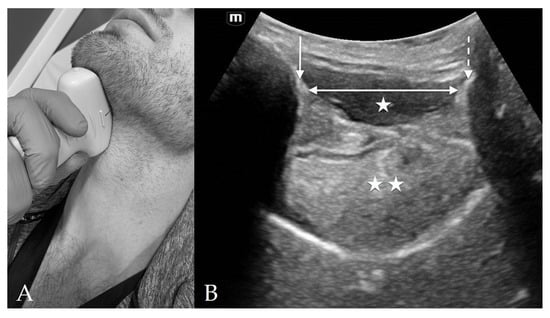

4.5. Suprasternal View

8. Preparation for Cricothyrotomy